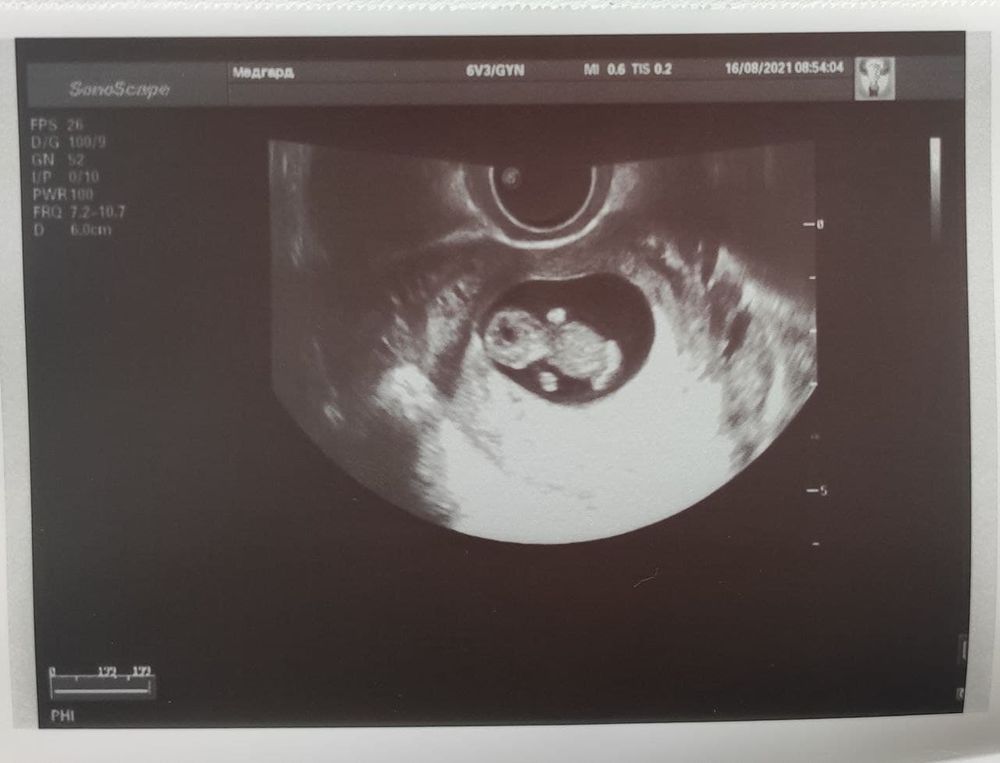

Утро началось с хороших новостей - я сделала УЗИ и выдохнула. До этого было 2 ЗБ, обе на 8-9 неделях, а сейчас на флюксуме уже 10 недель с сердцебиением. От звука сердечка немножко даже всплакнула. 171 удар в минуту) Он спал и не шевелился, я бы тоже с удовольствием поспала в девятом часу утра))

Размеры совпадают по сроку, сегодня 10нед1день.

Смешно было, когда гинеколог мне показывала ручки, потом ножки, а потом такая - смотри между ног, я думала там мальчик, а это пуповина)) Пуповина это даже еще трогательнее, ведь именно на этом этапе в прошлые разы что-то шло не так, а в этот раз получилось.